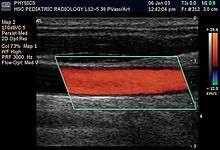

- Doppler mode: This mode makes use of the Doppler effect in measuring and visualizing blood flow

- Color Doppler: Velocity information is presented as a color-coded overlay on top of a B-mode image

- Duplex: a common name for the simultaneous presentation of 2D and (usually) PW Doppler information. (Using modern ultrasound machines, color Doppler is almost always also used; hence the alternative name Triplex.)

Doppler ultrasonography

Sonography can be enhanced with Doppler measurements, which employ the Doppler effect to assess whether structures (usually blood)[16] are moving towards or away from the probe, and its relative velocity. By calculating the frequency shift of a particular sample volume, for example flow in an artery or a jet of blood flow over a heart valve, its speed and direction can be determined and visualised. This is particularly useful in cardiovascular studies (sonography of the vascular system and heart) and essential in many areas such as determining reverse blood flow in the liver vasculature in portal hypertension. The Doppler information is displayed graphically using spectral Doppler, or as an image using color Doppler (directional Doppler) or power Doppler (non directional Doppler). This Doppler shift falls in the audible range and is often presented audibly using stereo speakers: this produces a very distinctive, although synthetic, pulsating sound.

It should be noted here that there are no standards for the display of color Doppler. Some laboratories show arteries as red and veins as blue, as medical illustrators usually show them, even though some vessels may have portions flowing towards and portions flowing away from the transducer. This results in the illogical appearance of a vessel being partly a vein and partly an artery. Other laboratories use red to indicate flow toward the transducer and blue away from the transducer. Still other laboratories prefer to display the sonographic Doppler color map more in accord with the prior published physics with the red shift representing longer waves of echoes (scattered) from blood flowing away from the transducer; and with blue representing the shorter waves of echoes reflecting from blood flowing toward the transducer. Because of this confusion and lack of standards in the various laboratories, the sonographer must understand the underlying acoustic physics of color Doppler and the physiology of normal and abnormal blood flow in the human body (see Red shift[17][18][19]).